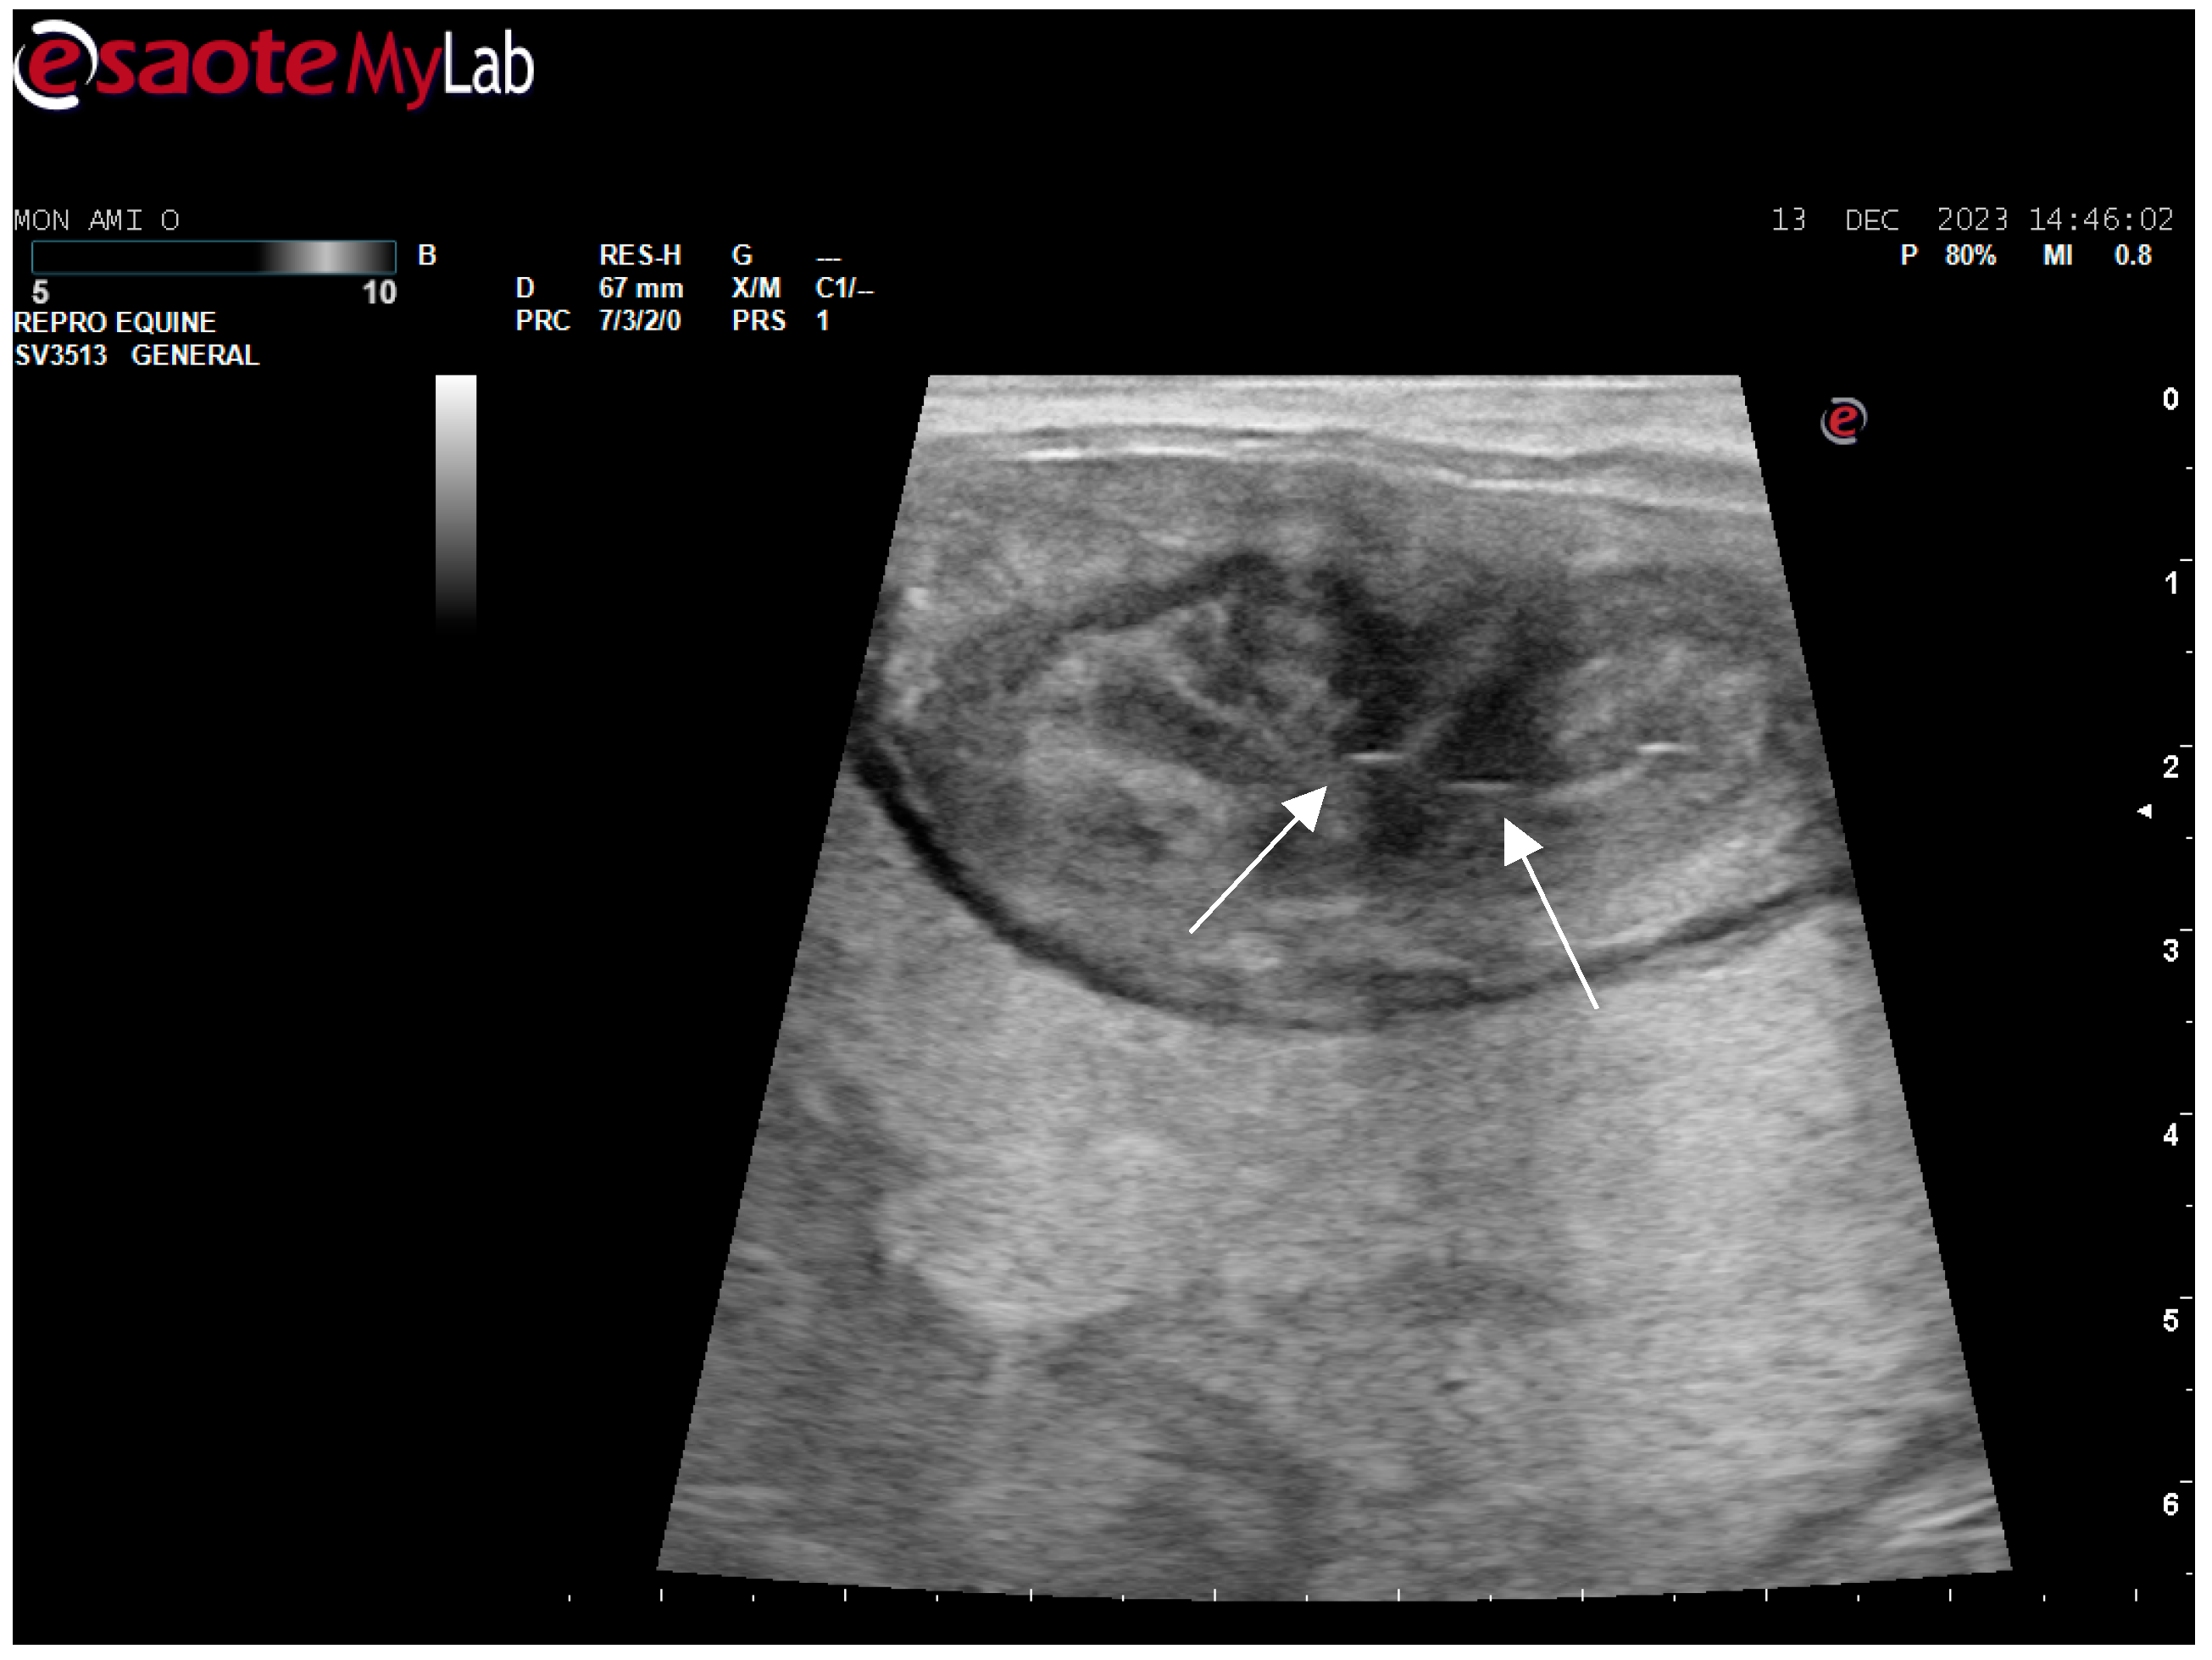

After surgery, the mare’s reproductive system was investigated. Ultrasonographically, slight uterine edema (grade 1 out of 5) and hyperechoic particles (Figure 2), suspected as air in the uterus, were observed. The left ovary was normal in size and echogenicity, present with some 10 to 28.4 mm follicles (Figure 3 and Figure 4). Due to poor perineal conformation, the mare had pneumovagina. Caslic’s vulvoplasty was performed.

Figure 2. Uterine edema (grade 1 out of 5) and hyperechoic particles (white arrows), suspected as air in the uterus.

Animals 14 01307 g002